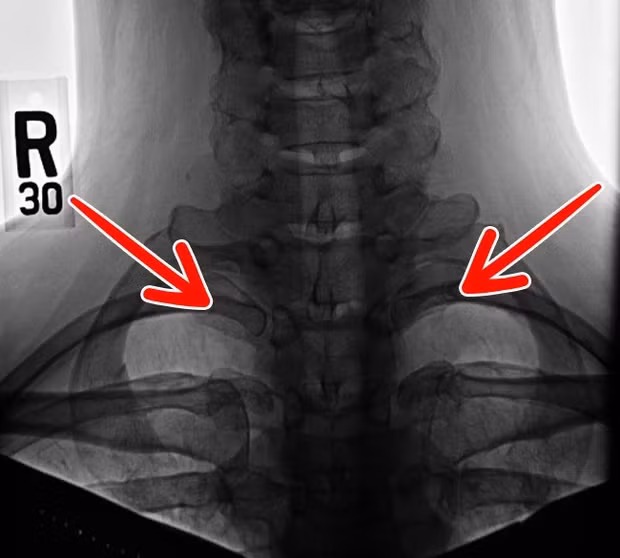

7. Xương sườn cổ: Khoảng 1% dân số thế giới có nhiều xương sườn hơn bình thường, kéo cả lên khu vực gần cổ. Theo Thuyết tiến hóa thì đây có thể là những gì còn sót lại từ thời kỳ khủng long lận, nhưng giờ thì chẳng còn tác dụng gì ngoài việc khiến chúng ta căng thẳng hơn và dễ gây bệnh về thần kinh.